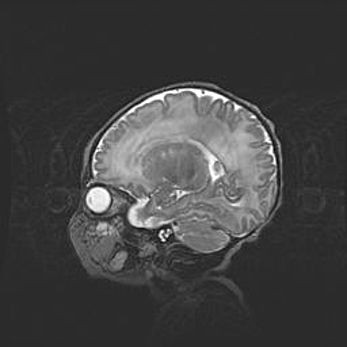

Мальформация Денди-Уокера. Киста задней черепной ямки.

Агенезия мозолистого тела.

Возраст: 2,5 месяца

Вес: 2420 г

Пол: женский

Окружность головы: 37 см

Срок гестации: 32 недели

Мальформация Денди—Уокера — редкий вид патологии ЦНС, представляющий собой врожденный порок развития каудального отдела ствола и червя мозжечка, ведущий к неполному раскрытию срединной (Мажанди) и латеральных (Лушка) апертур IV желудочка мозга. Для этогно синдрома характерна триада симптомов: гипотрофия червя мозжечка и/или полушарий мозжечка, кисты задней черепной ямки, гидроцефалия различной степени. В 70% случаев порок сочетается и с другими аномалиями головного мозга, в частности с агенезией мозолистого тела.